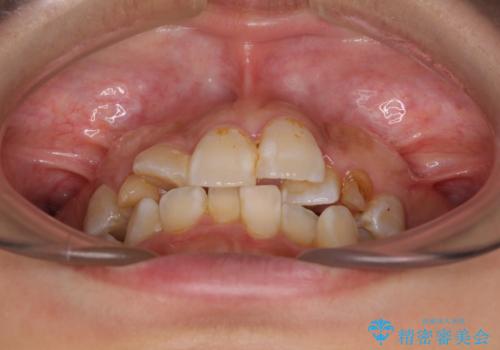

- 上下前歯のデコボコを気にして来院された患者様です。

上顎は両側の犬歯が骨内に埋伏しており、乳歯が残存している状態でした。

歯肉内に埋もれている場合には牽引することも可能ですが、両歯ともに骨内に完全に埋もれていたため、牽引することは不可能と判断しました。

口元の突出感があるわけではなく、叢生の程度もシビアではありませんでしたが、顎骨が小さく、左右ともに最後臼歯が歯肉に埋もれているため、下顎は左右第二小臼歯を抜歯することとしました。

上顎は左右ともに残存している乳歯を抜歯し、上下歯列を整えることとしました。